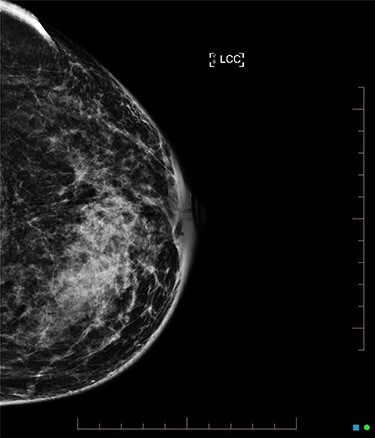

An ultrasound of the left breast demonstrated a 60-mm irregularity with no underlying collection at the 10 O’clock position, 2 cm from the nipple (Fig. 1). AB was treated with 5 days of oral flucloxacillin for presumed mastitis, and underwent a bilateral mammogram and ultrasound due to the suspicious irregularity of the left breast lesion. This showed an area of asymmetric density in the medial left breast with hyperemia (Fig. 2). The right breast showed two clusters of pleomorphic microcalcifications in the upper outer quadrant, further characterized as irregular lesions measuring 16 × 11 × 11 mm and 9 × 10 × 7 mm (Fig. 3).

Figure 2 .

Left breast mammogram features of granulomatous mastitis.